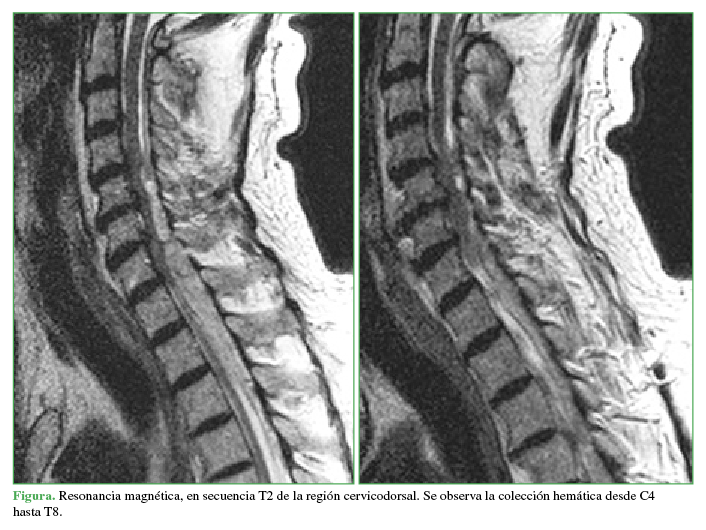

El hematoma epidural espontáneo es una entidad muy poco frecuente que supone una urgencia neurológica. Su presentación es muy variable, desde un dolor de espalda hasta una tetraplejia, según la gravedad y el nivel de compresión. Se comunica el caso de un paciente cardiópata de 71 años, tratado con acenocumarol, que presentó un hematoma epidural de modo espontáneo. Al inclinarse hacia el suelo, el paciente, que no tenía síntomas, sufrió un dolor brusco cervical seguido de debilidad en los miembros superiores e inferiores. Ante la sospecha clínica de una compresión medular, se decide realizar una resonancia magnética de urgencia, que mostró un hematoma de localización epidural con extensión desde C4 hasta T8. El diagnóstico urgente y el tratamiento de descompresión precoz son fundamentales para reducir al mínimo los daños neurológicos posteriores permanentes. AbstractSpontaneous spinal epidural hematoma is an uncommon condition and a neurological emergency. The clinical presentation of this type of hematoma is very variable, ranging from a backache up to a quadriplegia, according to the severity and the site of compression. Here, we discuss the clinical case of a 71-year-old patient with heart problems, under previous treatment with acenocumarol, that suffered a spontaneous epidural hematoma. The patient, previously asymptomatic, presented, sudden cervical pain when he bent over, followed by weakness in the lower and the upper limbs. Due to the clinical suspicion, an emergency MRI was performed, showing an epidural hematoma extending from C4 to T8. Early diagnosis and decompressive treatment are mandatory to minimize permanent neurological damage.Descargas